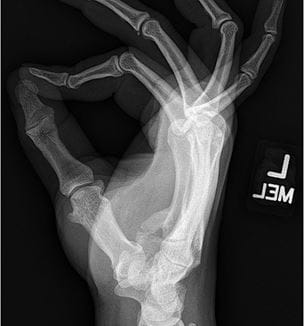

Unique Case Study Post-traumatic Heterotopic Ossification Results In Ulnar Nerve Compression

Innovations in Orthopaedics | Spring 2025